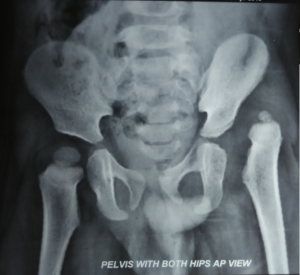

Now she is walking normally. And her parents are very happy!

congenital-hip-dislocation-xray